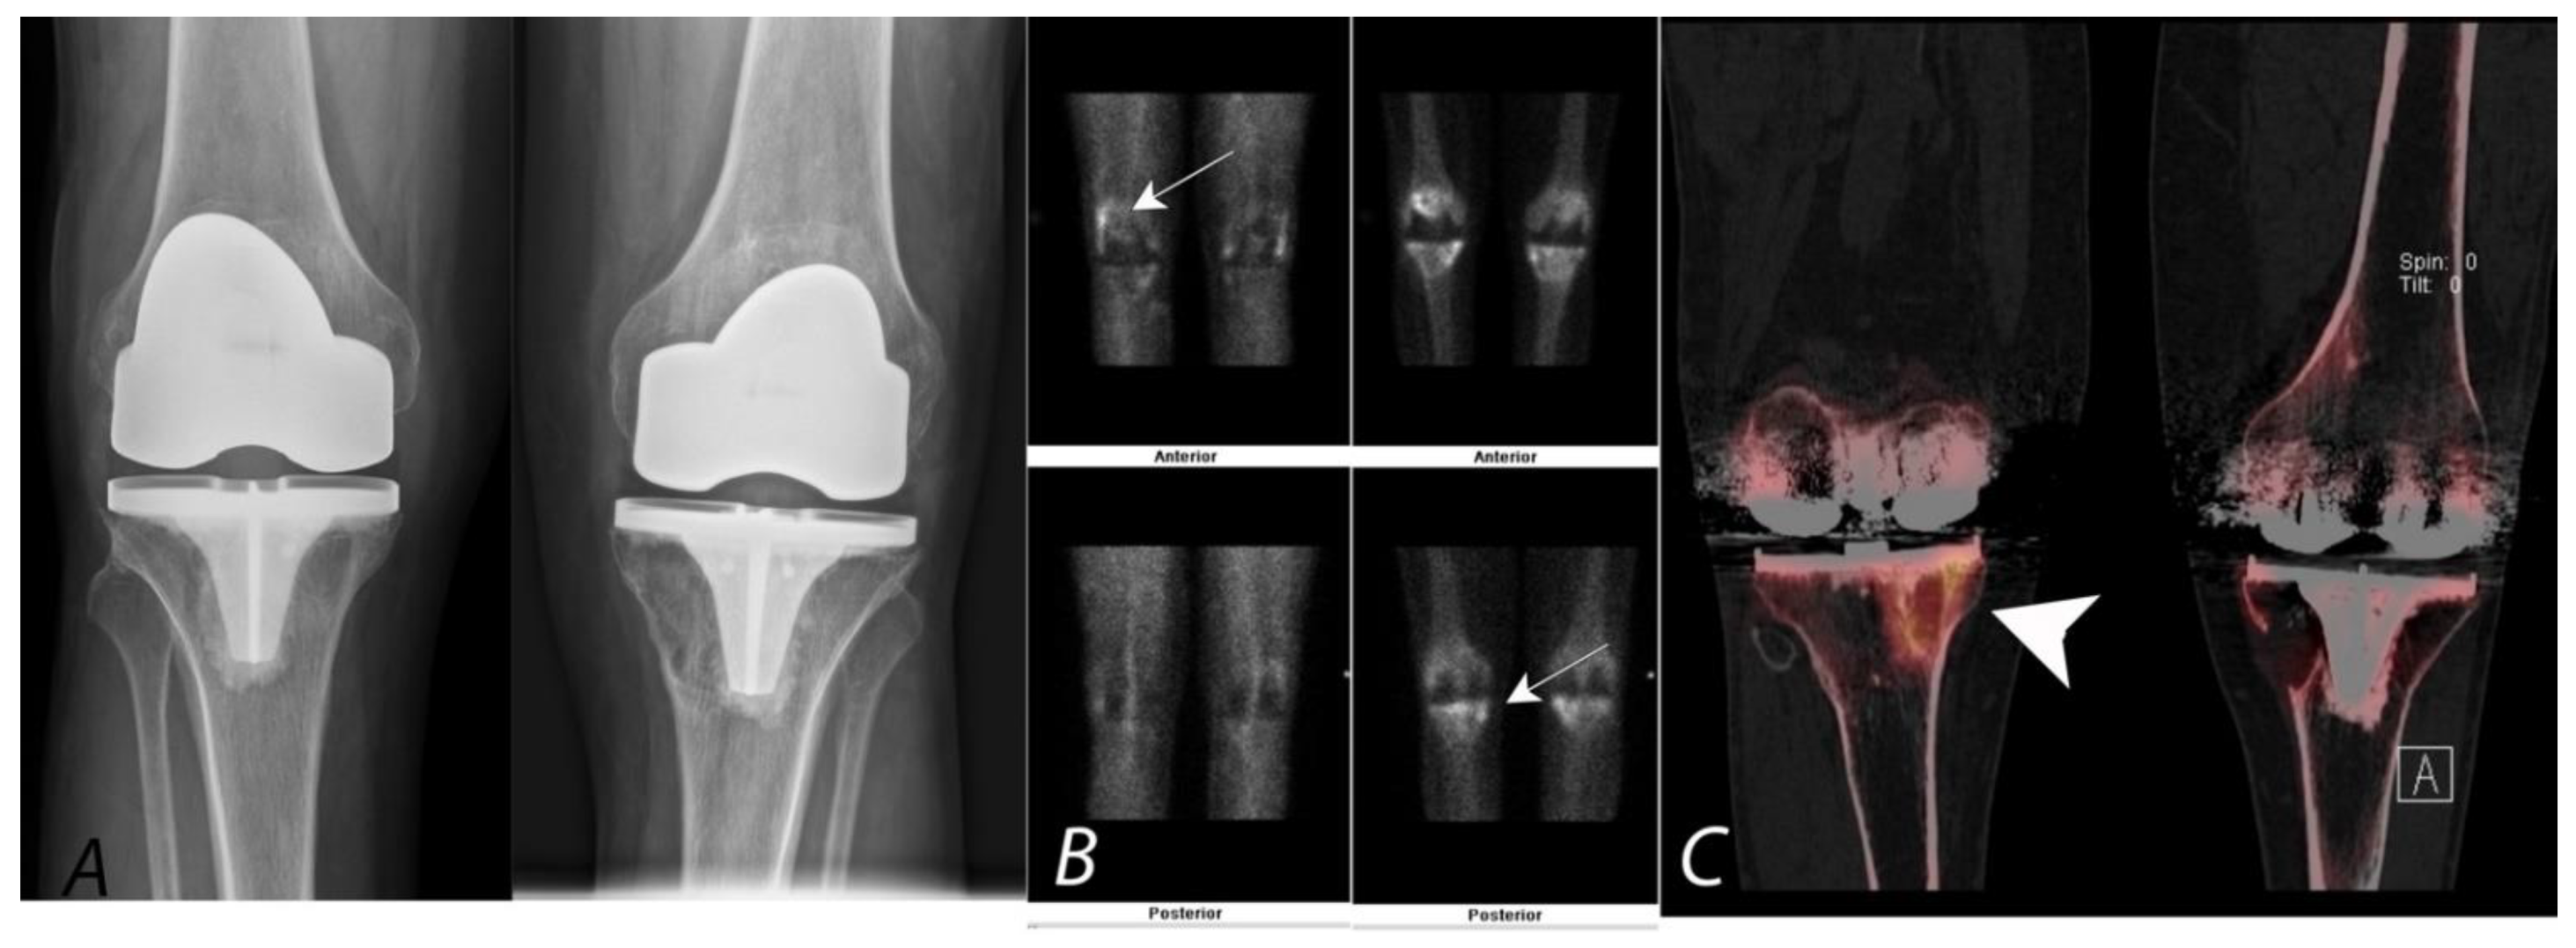

SPECT/CT, along with knee arthrography, can be used to evaluate soft tissue structures such as cartilage, menisci, and ligaments. This technique has been shown to be useful in the assessment of meniscal tears and injury to the ligaments, as well as in identifying intraarticular loose bodies within the knee joint [88,89,90]. SPECT/CT has also been shown to be useful in the evaluation of tumors around the knee joint and osteochondral defects and assessing remodeling at the sites of ligamentous repairs, as well as in the evaluation of patients presenting with pain after total knee arthroplasty [91] (Figure 8).

Figure 8.

Bilateral anterior AP radiographs, anterior and posterior planar blood pool and delayed mineral phase images and coronal SPECT/CT images of a Tc-99m MDP bone scan in a 65-year-old male with bilateral painful total knee protheses. Plain radiographs (A) are non-specific (and unchanged over several years) without defined peri-prosthetic lucency. Blood pool images and delayed images (B,C) demonstrate some hyperemia in the joint capsule and serpiginous areas of proximal tibial uptake (white arrows). Clarity is achieved by the SPECT/CT (coronal images, (C)), which demonstrates uptake associated with large, well-corticated areas of bone loss consistent with particle disease (white arrowhead). A similar well corticated region of lucency is also present in the medial aspect of the left proximal tibia.

SPECT/CT has become a very useful technique in the evaluation of painful knee status post knee arthroplasty and has recently been proposed as the second line of imaging modality after MRI in these patients. Even in asymptomatic patients, radiotracer uptake on planar and SPECT bone scans, specifically around the tibial component of the arthroplasty, can be a normal finding, even many years after the procedure. The addition of the CT component to SPECT significantly increases the specificity and accuracy of diagnostic interpretation by improving accurate localization of the uptake to a specific anatomic location [92,93]. For example, identification of the granulomatous process on CT can be a cause for non-specific diffuse uptake on bone scans. Additionally, in the absence of any anatomic abnormalities on CT, localized radiotracer activity below the medial aspect of the tibial component can be interpreted as physiological with a greater degree of confidence. The addition of other follow-up evaluation procedures, specifically if infection is suspected, may be required for complete assessment of painful knee after arthroplasty. SPECT/CT has been shown to be a highly valuable modality in this subset of patients, with alteration of management approach in up to 85% patients [92,93] (Figure 9).

Figure 9.

Fifty-year-old female with a painful left knee prothesis. Anterior planar (A), coronal CT (B) and coronal SPECT/CT (C) images of a Tc-99m MDP bone scan of both knees demonstrate a prominent increased uptake in a band surrounding the midportion of the left tibial prosthetic stem. Plain AP radiographs demonstrate sclerosis without periprosthetic lucency. Findings are consistent with being related to altered biomechanical remodeling (similar to a stress fracture). There is no evidence for loosening or infection.